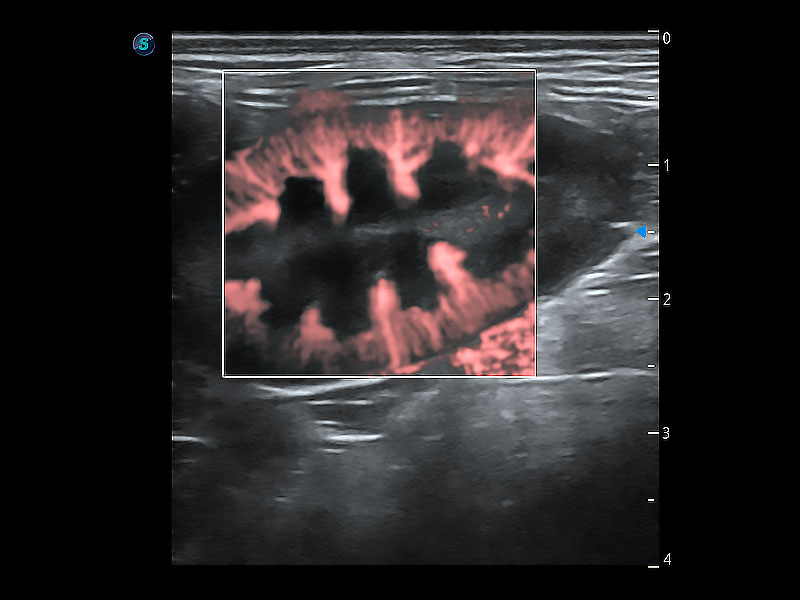

极大提升超低速微细血流的检出能力,同时更精准地滤除软组织和超声信号,为兽用医生提供以往无法通过常规血流获得的疾病诊断信息。